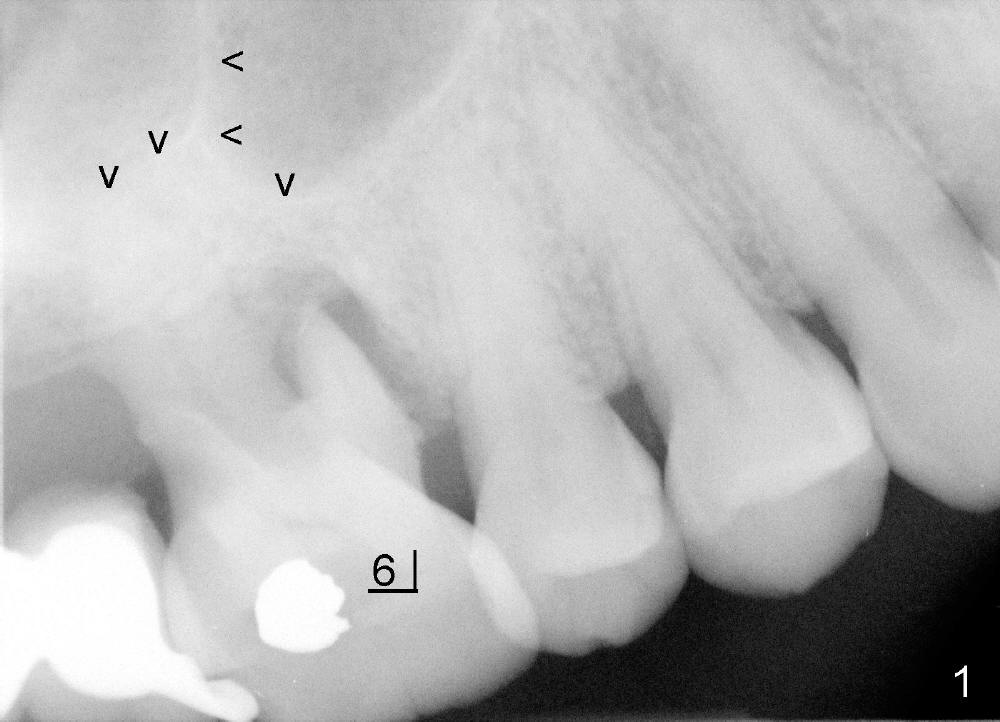

The upper right 1st molar of Mrs Chen has endo/perio disease (Fig.1). The bone height is limited (~ 3mm), but there is a sinus septum above (arrowheads). Approximately 4 months post extraction, a 6x11 mm implant is placed with insertion torque >60 Ncm, partially due to engagement into the sinus septum (Fig.2). There is apparent osteointegration 3 months postop (Fig.3).